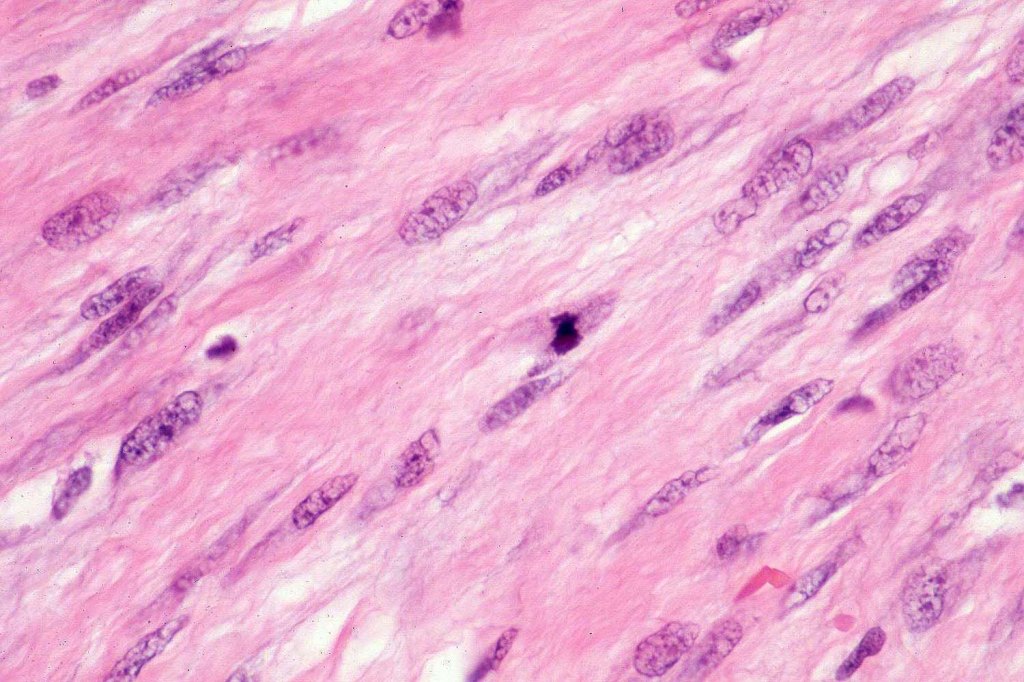

•Paucicellular spindle cell infiltrate with “myxoid” fine to a dense collagenous stroma

•Hyperchromatic nuclei